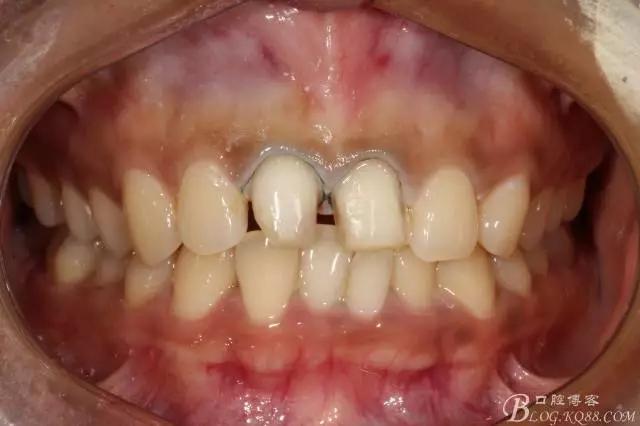

2016.1復(fù)查情況很不好,再次建議做瓷貼面并告知各自?xún)?yōu)缺點(diǎn)。這回患者同意并選擇鑄瓷貼面。

11扭轉(zhuǎn)明顯,擔(dān)心備牙過(guò)多,所以選取了一個(gè)模型,在石膏模型上先試備后,感覺(jué)還行。

備牙后11(因扭轉(zhuǎn)制牙有點(diǎn)多,還是露牙本質(zhì)了)